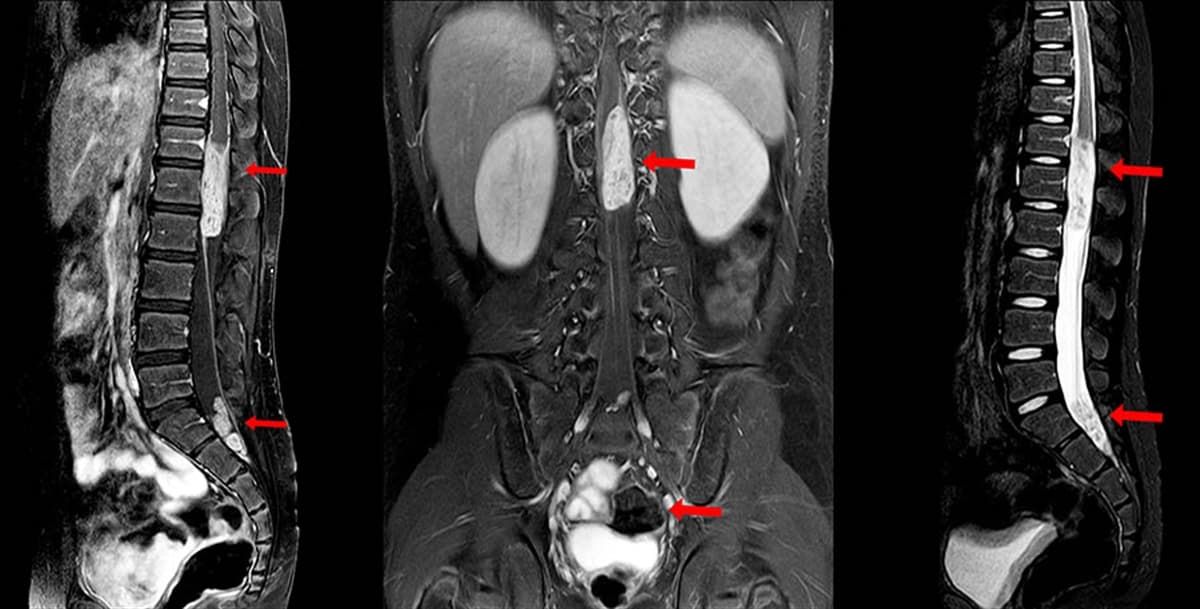

1. Spinal Manyetik Rezonans Görüntüleme (MRG)

Omurilik ve sinirlerin doğru görüntülerinin elde edilmesi işleminde MRG testi kullanılmaktadır. Dolayısıyla tümörün bulunduğu noktayı tespit etmede MRG testi önem taşımaktadır. Test sırasında belli dokuları vurgulamak amacıyla hastanın ön kolundaki veya elindeki damara kontrast bir madde enjekte edilebilir.

Test sırasında MRG tarayıcısı gürültülü bir ses çıkardığı için hastalara kulak tıkacı verilmektedir. Kişinin test sırasında aşırı kaygılanması durumunda sakinleştirici verilebilmektedir. Kimi durumlarda ise genel anestezi yapılmaktadır.